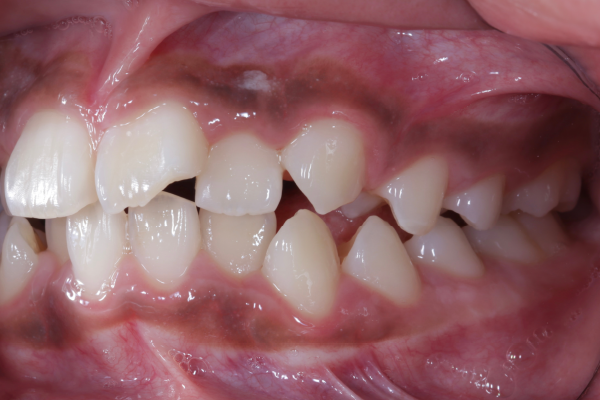

BEFORE

患者様は10代の女性で、前歯を中心とした歯並びのガタつき(叢生)を気にされて来院されました。できるだけ抜歯をせずに矯正治療を行いたいというご希望があり、精密検査を実施しました。

検査の結果、歯列全体のスペースバランスを調整することで、抜歯を行わずに歯並びの改善が可能と判断しました。歯の移動量やコントロール性を考慮し、今回はワイヤー矯正を用いた治療計画をご提案し、患者様にも十分ご理解いただいた上で治療を開始しました。